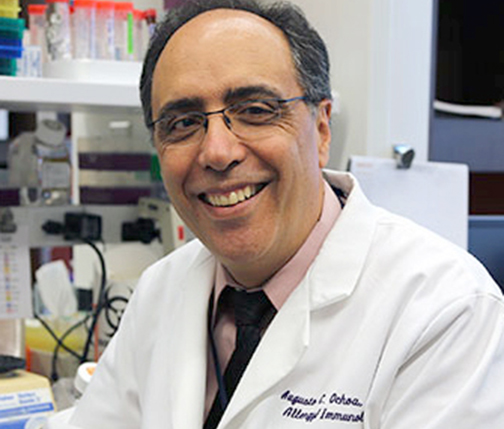

NCI Awards LSU Health’s Ochoa Most Prestigious Honor for His Leadership & Contributions to Community-Based Cancer Clinical Trials

The National Cancer Institute (NCI) chose LSU Health New Orleans’ Augusto Ochoa, MD, as the 2022 recipient of its most prestigious award honoring excellence in community-based cancer research. Dr. Ochoa received the Harry Hynes Award for Outstanding Contributions to Clinical Trials and Community Research on August 25, 2022, during the NCORP (NCI Community Oncology Research Program) Annual Meeting. More

Study Reports Blocking Key Enzyme Boosts Anti-Cancer T-Cell Responses and Resistance to Immunosuppression

A study led by LSU Health New Orleans cancer researchers describes a novel therapeutic strategy to overcome tumor-induced immunosuppression. For the first time, the research team identified a critical immunosuppressive pathway and a promising approach to intervene, protecting the ability of T-cells to attack cancer cells. Results are published in Frontiers in Immunology. More

LSU Health New Orleans Faculty Invited to Present at Cancer Moonshot Community Conversation

Dr. Augusto Ochoa, Deputy Director of the Stanley S. Scott Cancer Center and Chair of the Department of Interdisciplinary Oncology at LSU Health New Orleans School of Medicine, and Dr. Xiao-Cheng Wu, Professor of Epidemiology and Director of the Louisiana Tumor Registry at LSU Health New Orleans School of Public Health, were invited panelists for the Cancer Moonshot Community Conversation held on May 4, 2022. More